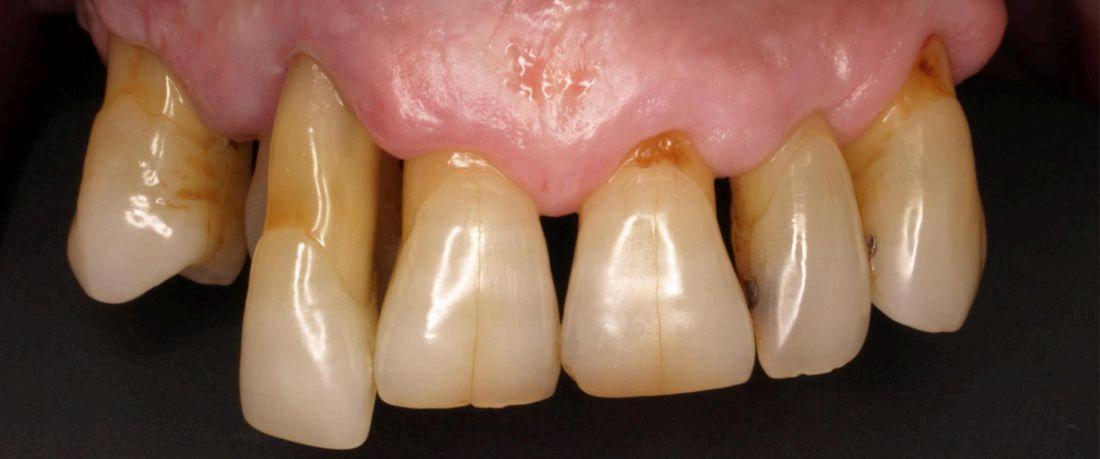

Es una infección grave de las encía que daña el tejido blando alrededor de los dientes. es una infección grave de las encías que daña el tejido blando alrededor de los dientes. Si no se trata, puede destruir el hueso en el que se apoyan los dientes, lo que puede causar que los dientes se aflojen o incluso se produzcan pérdidas dentales

Causa de la periodontitis

Si no tiene una buena higiene la placa y el sarro se acumulan en la base del diente, esto hace que la encia se inflame y esta misma se distancie de la superficie dentaria dando paso a una bolsa periodontal. Estas se llenan de bacterias provocando infecciones, si estas continuan con el tiempo, al final destruyen los tejidos y el hueso al rededor del mismo, asi perdemos estabilidad y sustencion de nuestro diente.

Sintomas

Encias rojas o inflamadas

Dolor, sangrado en las encias

Dientes flojos o sencibles